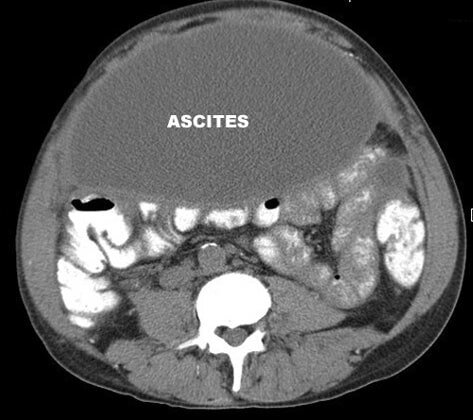

Асцит (водянка живота) – это скопление большого объема жидкости в брюшной полости. Болезнью это не считается, но является следствием прогрессирования серьезных заболеваний. Проявление асцита приводит к осложнениям, среди которых и тромбоз, поэтому не стоит игнорировать этот признак. Причиной появления водянки живота считается цирроз печени, опухоли брюшной полости, почечная и сердечная недостаточность. Избавиться от водянки живота можно лишь узнав причины ее появления и начав необходимое лечение.

Водянка живота – это наличие в брюшной полости жидкости, количество которой значительно превышает норму из-за нарушения обмена между кровью и тканями. В животе здорового человека всегда присутствует жидкость, которая распределяется по лимфатическим сосудам.

Увеличившийся в размерах живот является не единственным признаком брюшной водянки, поэтому после осмотра больного назначается дополнительная лабораторная и инструментальная диагностика. Присутствие жидкости в брюшной полости дает возможность отличить осложнение от ожирения.

Подтвердить асцит можно следующими методами исследования:

- локальное исследование органов ультразвуком;

- КТ или МРТ брюшной полости;